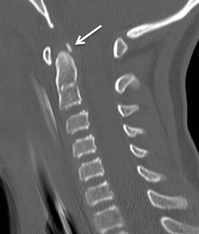

A persistent terminal bone fragment can be optimally visualized in imaging with a sagittal CT imaging of the cervical spine.

Ossiculum terminale CT

Sagittal CT imaging of a patient with a terminal ossicle (white arrow). Figure adapted from DOI: 10.1007/s00381-016-3199-7